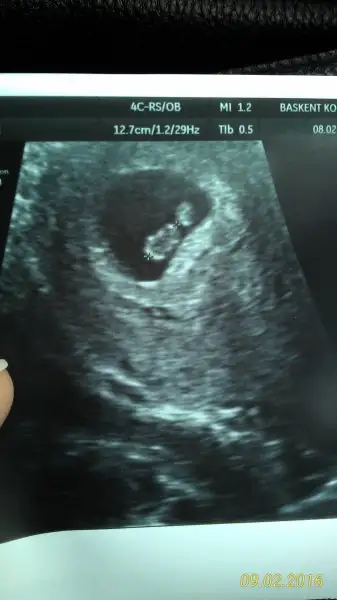

Canım bu da erkek yeğenimin karından usg, bunda da tutmuş mu bakar mısın, ben plasenta yerini anlamıyorum belli oldu

• IMG-20160210-WA0010.webp

IMG-20160210-WA0010.webp

19 KB · Görüntüleme: 499

plesanta solda karındansa ultrason erkek bunda da tutmuş cnm... kesenın patlıcanımsı görüntüsü yana çevrildiğinde solda kalıyor...